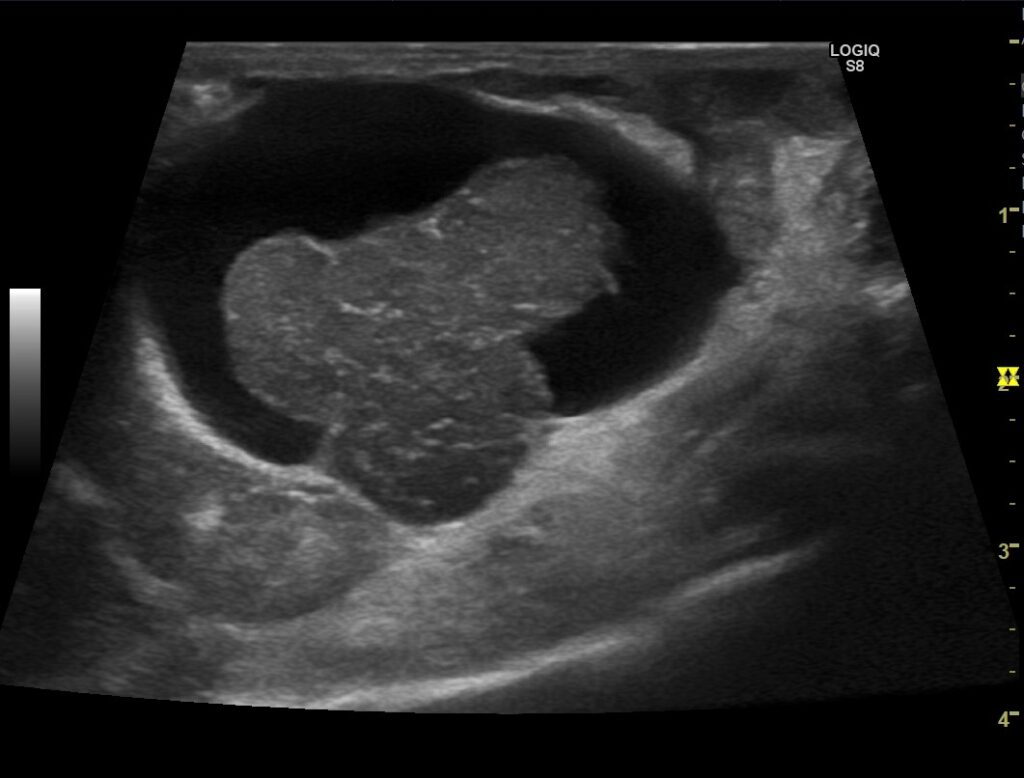

超音波検査によって発見されたゴールデンハムスターの子宮腫瘍の画像。